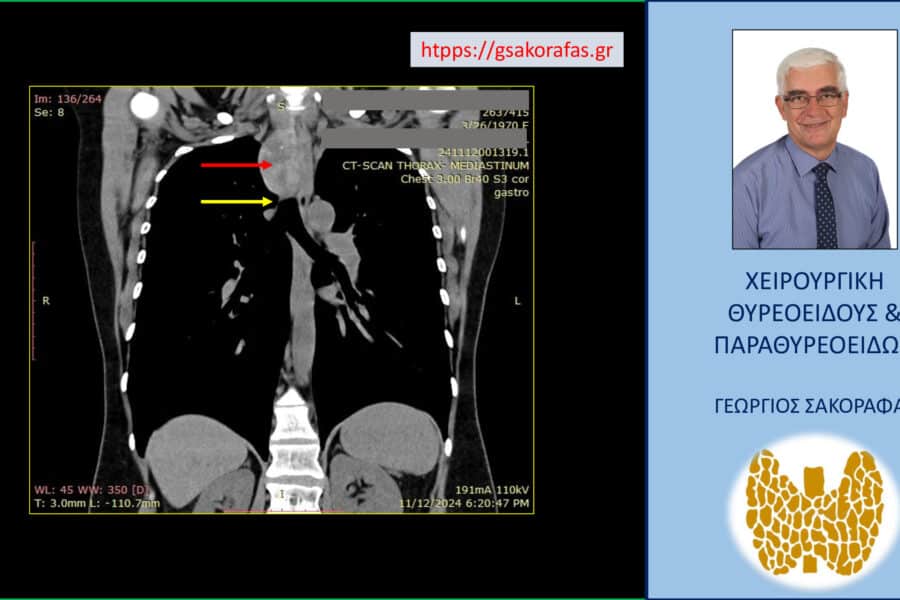

Όζοι θυρεοειδούς και συμπληρωματική θυρεοειδεκτομή (completion thyroidectomy) – με αφορμή ασθενή μας Παρουσίαση ασθενούς Αιτία…